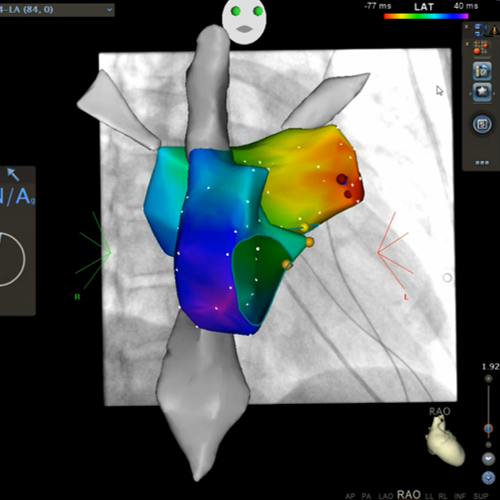

So können mit sogenannten 3 dimensionalen Ortungssystemen (Mappingsystemen – CARTO® 3 System, Enside® System) die Herzrhythmusstörungen erfasst werden und die elektrische Erregung des Herzens in einem dreidimensionalen Computermodell dargestellt werden (vergleichbar mit einer elektrischen Landkarte der Herzrhythmusstörung mit frühen und späten elektrischen Arealen). Darüber hinaus kann der elektrische Impuls des Herzens in seinem Ablauf dargestellt werden. Dieses erleichtert den Mechanismus der Herzrhythmusstörung zu erkennen und den Ursprungsort der Herzrhythmusstörung punktgenau zu erfassen.

Bild 1a und 1b: Dreidimensionale, virtuelle Darstellung der Herzvorhöfe (farbig) und der großen Venen (grau) mit CARTO 3 Uniview®.

Dargestellt sind ein rechtsseitlicher (Bild 1a) und linksseitlicher (Bild 1b) Blick auf das Herz mit Röntgenbild im Hintergrund (Bild 1a). Die Vorhofherzrhythmusstörung bei diesem Patienten hatte seinen Ursprung im linken Herzvorhof dargestellt durch die rot-orange Farbe, welche die früheste elektrische Erregung kodiert während die violette Farbe die späteste elektrische Erregung während des Herzzyklus darstellt. Die roten Punkte stellen den Ort dar, an dem die Herzrhythmusstörung unter Verödung aufhörte.

Bild 2: virtuelle Darstellung des linken Herzvorhofs mit angrenzenden Lungenvenen.

Die Farben kodieren den Ablauf der elektrischen Erregung des Herzens während eines Herzschlages mit frühen (rot-orangen) und späten (violetten) Bereichen beide Bereiche grenzen aneinander (rote Trennlinie). Somit kreist diese Rhythmusstörung um die Herzklappe (Mitralklappe – Öffnung in dem Modell des Herzvorhofes).